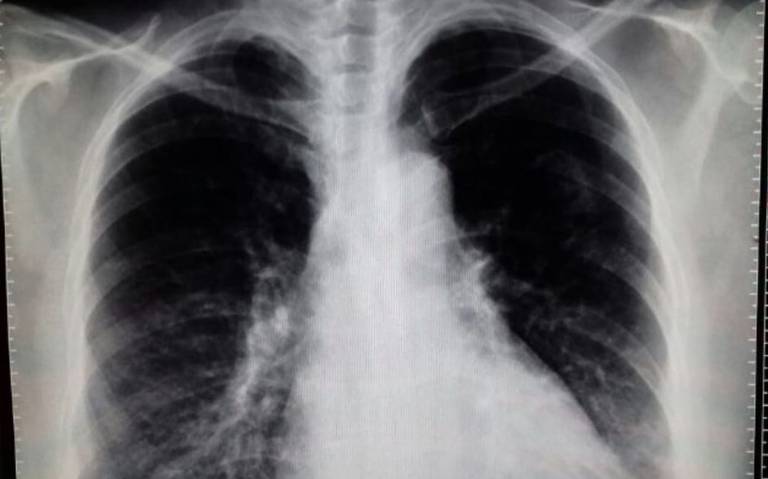

Los antidepresivos se asociaron con un mayor riesgo tanto de neumonía como de exacerbación en pacientes con EPOC, disminuyendo los riesgos al suspender el tratamiento. Estos hallazgos sugieren una estrecha vigilancia de los efectos secundarios de la prescripción de antidepresivos y la consideración de intervenciones no farmacológicas. Thorax, 19 de junio de 2023